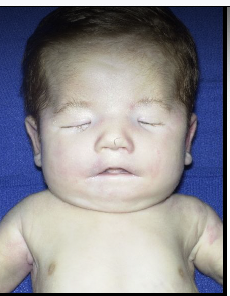

trisomy 13 - patau syndrome

microcephaly

mental retardation

microphthalmia

polydactyly

cardiac defects

umbilical hernia

renal defects

cleft lip/palate

rocker bottom feet

**majority die in utero